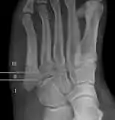

Diagnostic X-rays include anteroposterior, oblique, and lateral views and should be made with the foot in full flexion.

Proximal fractures of the fifth metatarsal bone:

- Proximal diaphysis, typically stress fracture.[12][13]

- Metaphysis: Jones fracture[14]

-Tuberosity: Pseudo-Jones fracture[15] (avulsion fracture).[15]

Pseudo-Jones fracture